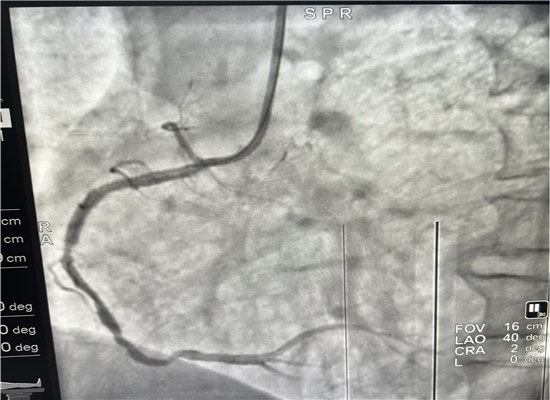

早上8时48分,120急救中心接到六麻卫生院的出诊电话,有一名胸痛病人7时左右在家晕倒,家属急送到六麻卫生院,初诊为急性心肌梗塞,病情危重,需马上转院到我院进一步治疗。急诊医学科立即启动急性心肌梗塞救治绿色通道预案,立即出车,于9时40分到达六麻卫生院,到诊后复查心电图并立即上传微信群会诊,确诊后为患者按急性心肌梗死急诊介入治疗做准备,监护返回。提前通知心血管内科医师到急诊医学科等侯会诊,并同时激活导管室。10时45分患者顺利转运回我院,心内科医师会诊后快速完成知情谈话及签字,10时57到达导管室,由杨勇、张轩两位主任进行介入手术,术中发现患者右冠状动脉100%闭塞,11时46分顺利植入一枚支架,患者的心肌得以重新灌注,11时58分手术结束,术后患者胸痛症状明显缓解,12时12分转到CCU监护。

介入手术前